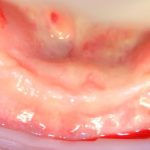

б) достаточные объемы кератинизированной десны, не будет проблем с герметичностью раны (фактор #3)

этого уже достаточно, чтобы планировать и нормально провести остеопластическую операцию: